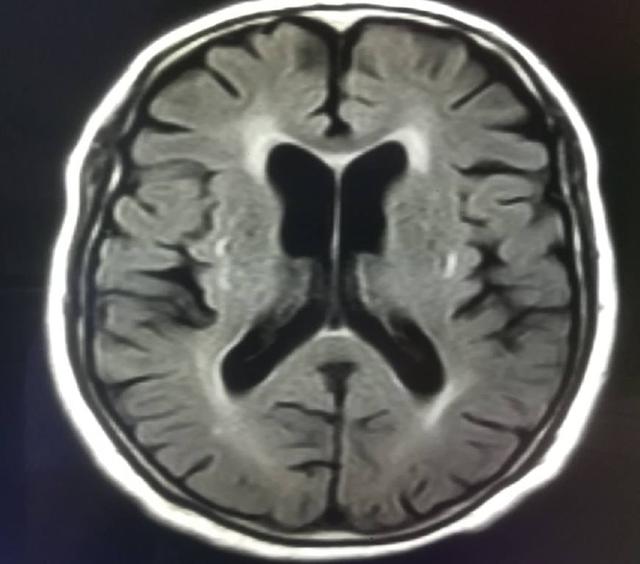

腦萎縮指腦容量或腦組織體積變小,多指影像學(xué)的一些表現(xiàn),如頭顱CT、頭顱核磁共振發(fā)現(xiàn)腦組織縮小,它包括生理性腦萎縮及病理性腦萎縮。生理性指隨著年齡的增長而使腦組織小于正常值;病理性腦萎縮則是由非正常因素導(dǎo)致腦組織萎縮,從而使患者呈現(xiàn)一些特定的癥狀,那么腦萎縮會(huì)影響壽命嗎?